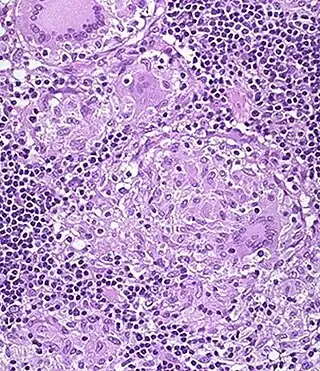

![]() Sección H&E de granuloma no caseado, en el colon de paciente con la enfermedad de Crohn | ||